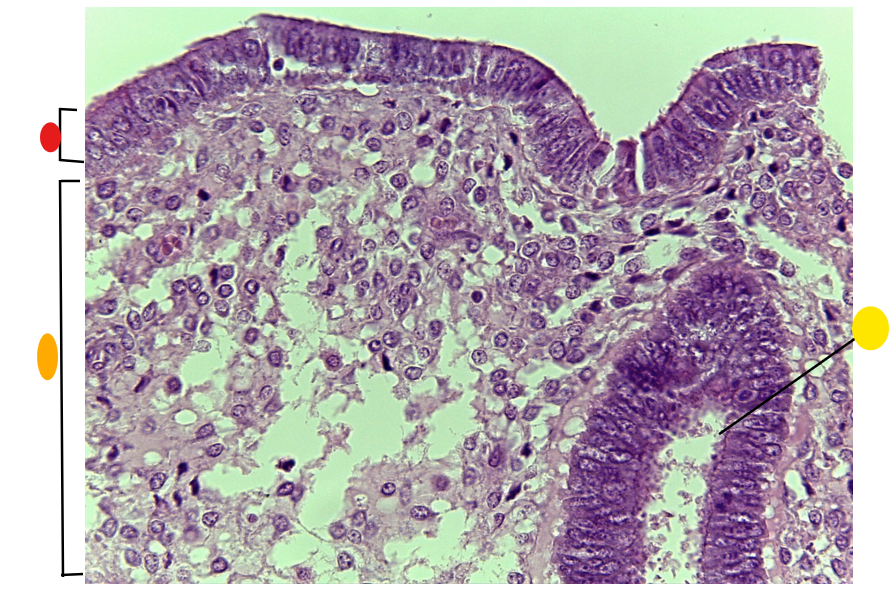

red

granulosa cells

orange

thecal cells

yellow

primary or secondary oocyte

light green

cumulus oophorus

dark green

antrum

what is this

tertiary follicle